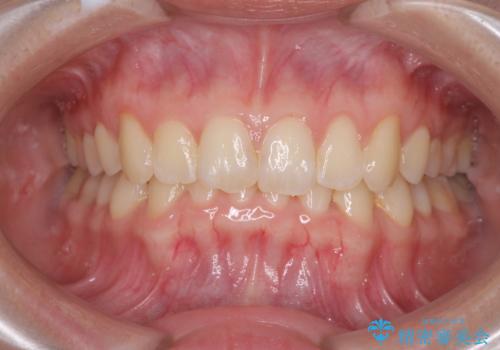

- 上下前歯の叢生と八重歯を気にして来院された患者様です。

前歯部叢生のスペースを獲得するため、上下顎左右小臼歯各1歯を抜歯することとしました。

歯列はきれいに整いますが、歯肉ラインは治療前の歯肉の位置を踏襲します。

特に八重歯であった歯は歯冠が長く見えますので、改善を希望される場合には、歯肉移植術を行う必要があります。